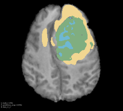

Deep neural network models used for medical image segmentation are large because they are trained with high-resolution three-dimensional (3D) images. Graphics processing units (GPUs) are widely used to accelerate the trainings. However, the memory on a GPU is not large enough to train the models. A popular approach to tackling this problem is patch-based method, which divides a large image into small patches and trains the models with these small patches. However, this method would degrade the segmentation quality if a target object spans multiple patches. In this paper, we propose a novel approach for 3D medical image segmentation that utilizes the data-swapping, which swaps out intermediate data from GPU memory to CPU memory to enlarge the effective GPU memory size, for training high-resolution 3D medical images without patching. We carefully tuned parameters in the data-swapping method to obtain the best training performance for 3D U-Net, a widely used deep neural network model for medical image segmentation. We applied our tuning to train 3D U-Net with full-size images of 192 x 192 x 192 voxels in brain tumor dataset. As a result, communication overhead, which is the most important issue, was reduced by 17.1%. Compared with the patch-based method for patches of 128 x 128 x 128 voxels, our training for full-size images achieved improvement on the mean Dice score by 4.48% and 5.32 % for detecting whole tumor sub-region and tumor core sub-region, respectively. The total training time was reduced from 164 hours to 47 hours, resulting in 3.53 times of acceleration.